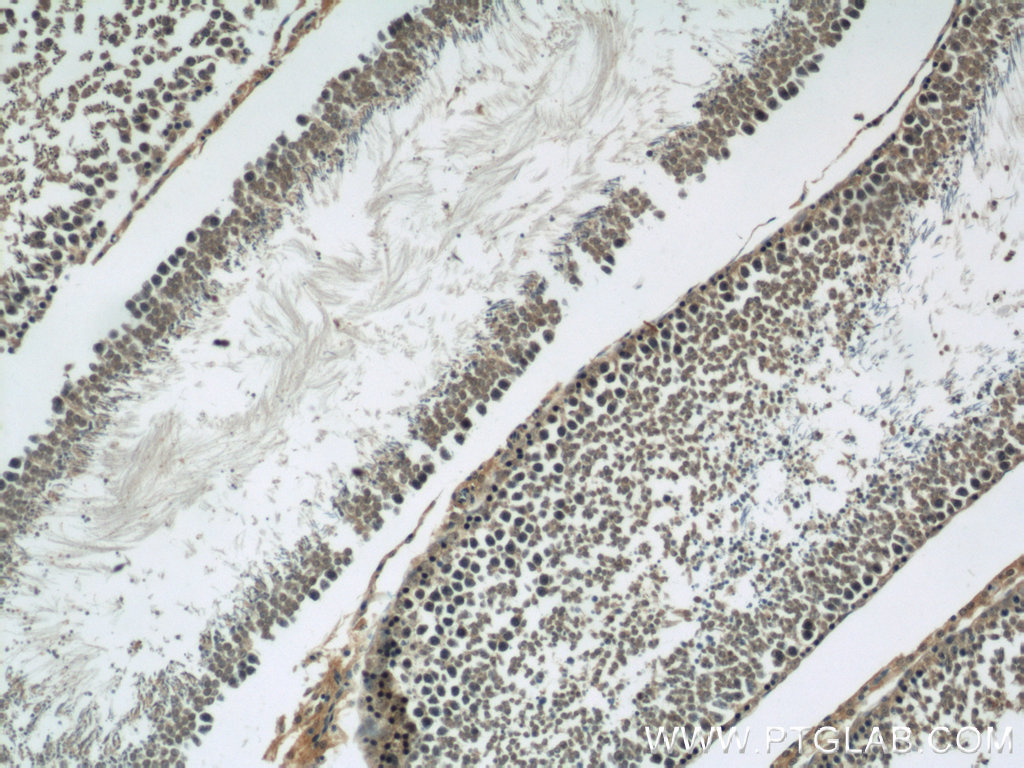

| Positive IHC detected in | human breast cancer tissue, human testis tissue, rat testis tissue Note: suggested antigen retrieval with TE buffer pH 9.0; (*) Alternatively, antigen retrieval may be performed with citrate buffer pH 6.0 |

| Immunohistochemistry (IHC) | IHC : 1:20-1:200 |